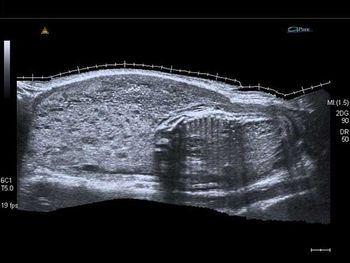

What is your diagnosis in this woman who presents with right hemipelvis pain?